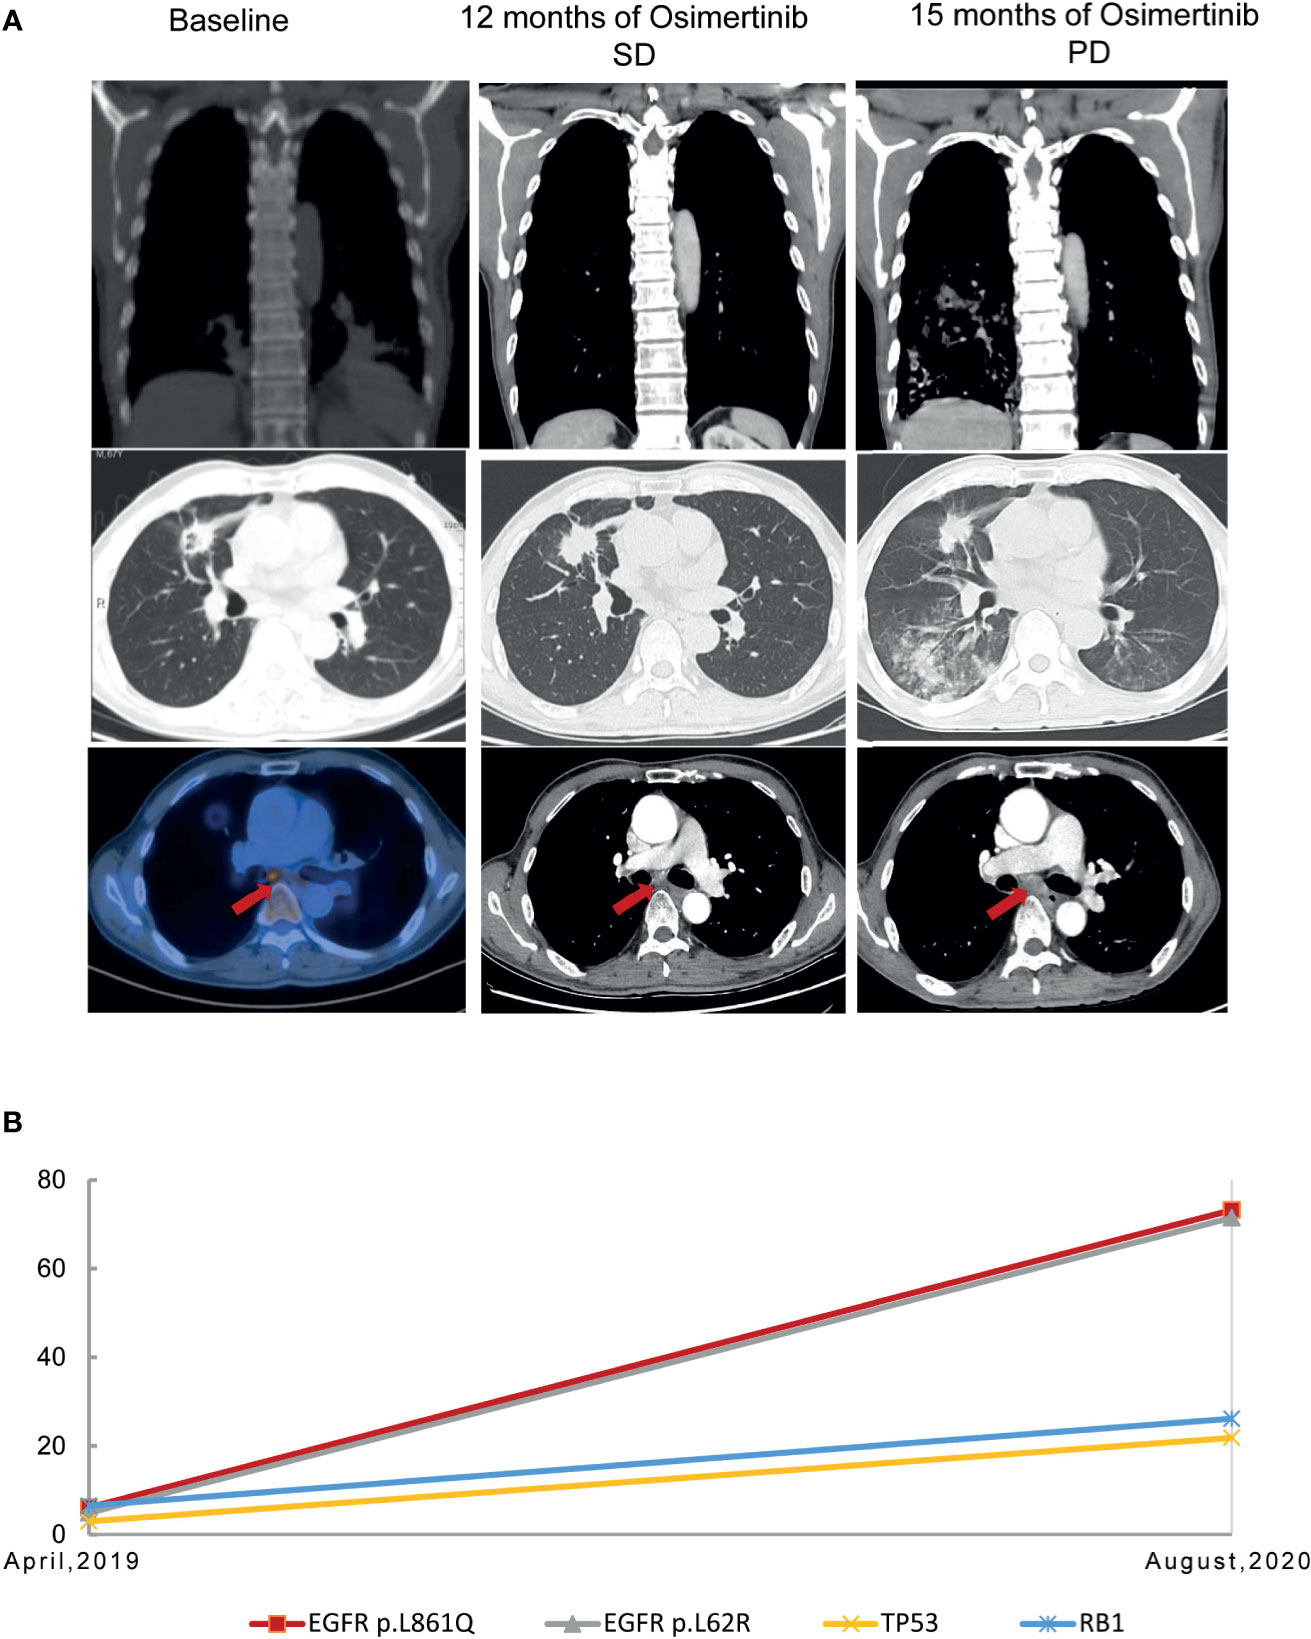

A 68-year-old, nonsmoker, male presented with a history of back pain for two months; no family history of tumor was reported. Positron emission tomography-computed tomography (PET-CT) revealed a fluoro-2-deoxy-d-glucose (FDG)-positive lesion in the left middle lung lobe and metastases in multiple bones (Figure 1A). CT-guided core needle biopsy of the tumor revealed adenocarcinoma with positivity for CK7 protein and TTF-1 staining (Figure 1B). To identify potentially actionable mutations of the patient, paired NGS‐based genetic testing of 1,021 cancer‐related genes was performed with both circulating free DNA from plasma and DNA extracted from the leukocytes (Geneplus‐Beijing Ltd., Beijing, China). EGFR L861Q mutations (allelic fraction, AF=6.1%) in exon 21 were identified by next-generation sequencing (NGS) of the plasma, with concurrent TP53 N239S mutation in exon 7 and RB1 mutations (Figure 1C). First-line therapy with osimertinib (80 mg daily) was initiated. He achieved stable disease condition with decreasing primary lesions, confirmed based on the Response Evaluation Criteria in Solid Tumors 1.1. The patient also showed significant improvement in terms of back pain and quality of life, and the adverse events were well tolerated. He experienced progressive disease of the right frontal lung lobe, subcarinal lymph node, and brain metastases after a progression-free survival (PFS) of 15.0 months (Figure 2A). Subsequently, the patient presented with severe cough, headache, and back pain.

FIGURE 2

www.frontiersin.org

Figure 2 Representative computed tomography images at various points (A) and mutation analysis of the patient’s plasma (B) before and after osimertinib treatment.

Due to the infeasibility of obtaining additional tissue biopsy, liquid biopsy assessing circulating tumor DNA (ctDNA) by NGS was performed. The AF of the L861Q mutation increased to 73.2%, with TP53 and RB1 mutations and absence of EGFR T790M (Figure 2B). Subsequently, the patient was treated with pemetrexed and carboplatin plus bevacizumab as second-line therapy. After two cycles of chemotherapy, he experienced significant improvement in headache, cough, and back pain, but experienced fatigue. However, the patient refused to continue chemotherapy because of personal reasons. The last follow-up was in November 2020, after which the patient passed away, with an overall survival of 19 months (Figure 3).